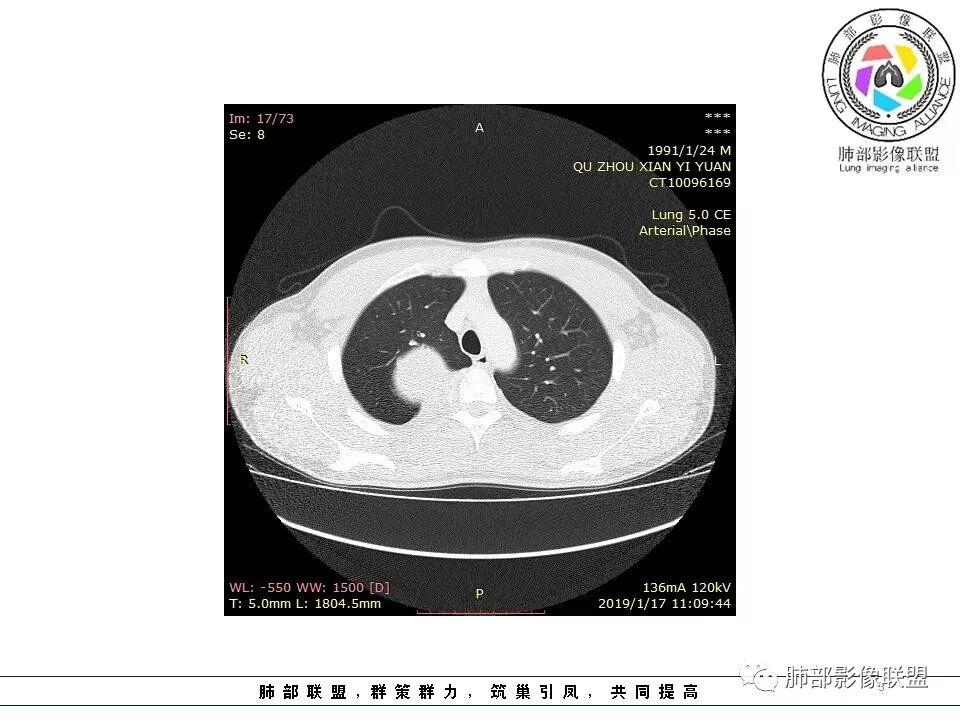

后纵隔脊柱旁占位性病变,疾病谱有神经鞘瘤,sft,节细胞瘤,髓外造血。此例有胸膜尾征,蛇纹征 ,延迟强化。考虑胸膜孤立性纤维瘤。看到有供血动脉,但不知道是哪里的血管。

后纵隔类圆形新生物,边缘光滑,胸膜尾征明显,贴近脊柱,蛇纹,血供丰富,考虑后纵隔软组织肿瘤,具体类型看不出来,鉴别神经鞘瘤。

后纵隔脊柱旁占位性病变,有胸膜尾征,胸膜下脂肪可见,蛇纹征,明显强化。考虑孤立性纤维瘤。

右侧后纵隔脊柱旁占位,边缘光滑清晰,内侧肺组织受压,外侧可见胸膜尾征,增强持续强化,并可见蛇纹血管征。考虑SFT

青年男性,右侧后纵膈肿块,有胸膜尾征,支气管被推压,定位肺外,脏胸膜?血供来自肺动脉及肋间动脉,增强后有强化,蛇纹征,考虑SFT,鉴别鞘瘤

右肺占位,跨越上叶后段、下叶背,边缘光滑,瘤肺界面清,见肺压缩缘(线样不张`强化),见胸膜尾征,胸膜下脂肪未见明显增厚,肋骨丶脊柱未见侵袭及受压,渐进性丶地图样强化,冠状位似见体循环供血

诊断:SFT(来源壁层胸膜?一般小于20%)

鉴别:神经源性(鞘瘤)、LCD、肉瘤丶孤立性间皮瘤

右侧后纵膈肿块,有胸膜尾征,周围肺组织及支气管被推压,定位肺外,脏层胸膜来源,血供来自肺动脉或者支气管动脉,增强后持续渐进强化,蛇纹征,考虑SFT,鉴别鞘瘤。

青年男性,右后上纵隔脊柱旁沟可见团状软组织影,边界清,密度尚均匀,推挤邻近肺组织,胸膜可见掀起,有肺动脉供血,增强轻度蛇皮样强化,纵隔淋巴结未见肿大,邻近骨质未见破坏,胸膜下脂肪间隙消失,考虑SFT孤立性纤维瘤可能性大,鉴别神经鞘瘤,节细胞瘤,建议活检。

青年男性,胸痛,右上纵膈脊柱旁肿块,形态光整规则,支气管被推移,临近的胸膜明显增厚,有胸膜掀起,增强后密度不均匀,可见蛇形血管征,血供似乎有两根血管供血,考虑SFT

边缘光滑,宽基底与胸壁相连,跨叶裂,叶裂稍前推,血管、支气管前移。

浅分叶

外上侧少量胸水

肋间动脉供血,强化尚均匀,逐步强化